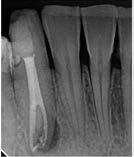

The canals were initially instrumented with a size #15 K-file, and coronal flaring was carried out using Gates Glidden burs (numbers 3 and 2; Dentsply Maillefer, Ballaigues, Switzerland). Biomechanical preparation was completed by using rotary nickel-titanium files ProTaper Gold (Dentsply Maillefer, Ballaigues, Switzerland) up to apical file size # 30. Copious irrigation with 3% sodium hypochlorite (NaOCl) with ultrasonic Endo Activator (Dentsply Maillefer, Ballaigues, Switzerland) was applied for 30 second followed by 17% Ethylenediaminetetraacetic acid (EDTA) for 1 minute with safe 2-side vents irrigation tips IrriFlex (Produits Dentaires, Swizterland), to remove the inorganic tissues, and this was performed during the instrumentation phase. Sterile paper points were used to dry the root canals. Master cone radiograph was taken, and the two canals were obturated with Tubli-seal (Kerr UK, Peterborough, U.K.) and laterally condensed using gutta-percha points. Final radiographs were taken to ensure proper obturation. A sterile cotton pellet was then placed in the pulp chamber, and IRM cement (Dentsply De Trey GmbH, Konstanz, Germany) was applied to seal the access cavity as a temporary filling to prevent coronal leakage. The patient was referred for final restoration (Fig. 2)